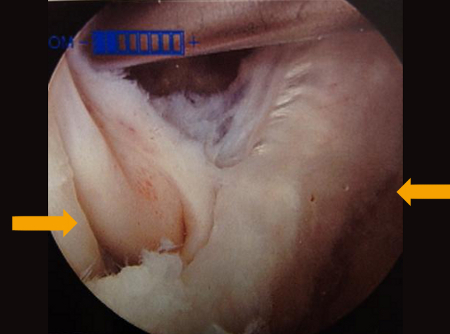

Interval of medial gastrocnemius and semimembranosus viewed with arthroscope

From the collection of Dr John D. Kelly IV; used with permission

MRI depicting cyst in interval of medial gastrocnemius and semimembranosus